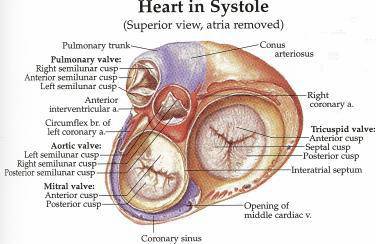

The tricuspid valve consists of three flaps or leaflets however cases are found when the tricuspid valve consists of only two or even four leaflets instead of the traditional three. The tricuspid valve lies within the right trigone.

The space in between the septal insertion of the tricuspid valve and the septal insertion of the anterior leaflet of mitral valve belongs to the membranous septum that separates the left ventricle from the right atrium.

Tricuspid valve anatomy. An appreciation of the complex and variable anatomy of the tricuspid valve is essential to unraveling the pathophysiology of tricuspid regurgitation. It is the atrioventricular valve that allows blood to flow from the right atrium to the right ventricle. Then blood exits the heart via the pulmonary artery.

Anatomy of the tricuspid valve. The tricuspid valve complex consists of the annulus leaflets right ventricle papillary muscles and chordae tendinae. Right atrioventricular valve tricuspid valve these are large veins that transport deoxygenated blood from the body back to the heart.

A greater appreciation of normal and abnormal anatomy is important as new methods of treating the tricuspid regurgitation are developed. It opens during diastole and closes during systole. The tricuspid valve tv is a complex structure.

B the relevant anatomy shown from the front view. The tricuspid valve lies between the right atrium and the right ventricle and is placed in a more apical position than the mitral valve. The tricuspid valve has an area of 4 to 6 cm square and is located between the right atrium and the right ventricle of the heart.

The valve has anterior posterior and septal leaflets cusps the bases of which attached around the av orifice to the fibrous ring fibrous skeleton of the heart. Blood collects within the right atrium and it must flow through the tricuspid valve in order to enter the right ventricle. The tricuspid valve functions as a one way valve that closes during ventricular systole to prevent regurgitation of blood from the right ventricle back into the right atrium.

A the anatomy of the tricuspid valve and adjacent structures from a surgical view. Anatomy of the tricuspid valve. The tricuspid valve anatomy shows greater variability than the anatomy of the mitral valve.

In normal heart the tricuspid valve is located slightly closer to the apex than the mitral valve. The red dotted lines show the direction of dilation of various structures in the setting of secondary tricuspid regurgitation. Unlike the aortic and mitral valve it is not possible to visualize all tv leaflets simultaneously in one cross sectional view by standard two dimensional echocardiography 2de either transthoracic or transesophageal due to the position of tv in the far field.

It opens during ventricular diastole allowing blood to flow from the right atrium into the right ventricle.